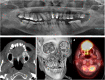

Primary oral leiomyosarcoma of the maxillary bone and sinus: case report and up-to-date review of literature